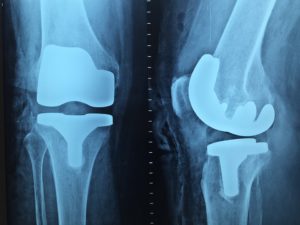

Os exames de raio X são comumente usados para analisar fraturas em diversas partes do corpo, pois com ele, os ossos são facilmente capturados e é possível ver com precisão se há alguma anomalia. Em alguns órgãos como o pulmão, por exemplo, também é possível identificar se há alguma anomalia ou doença através desse tipo de exame.